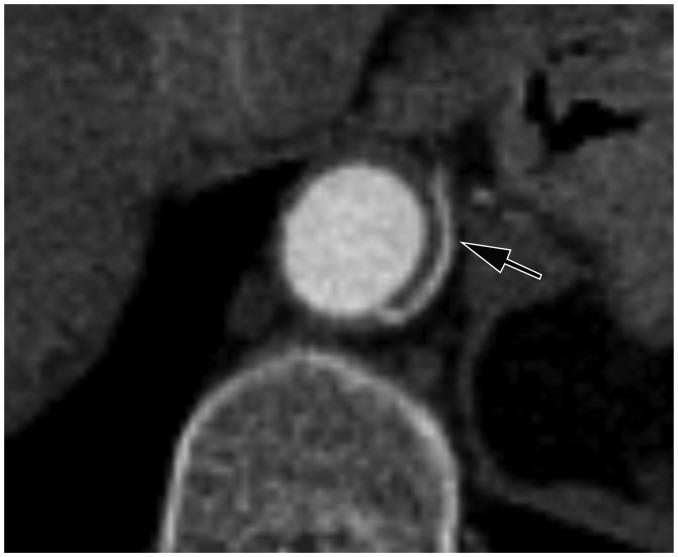

Early-Branched Short Renal Arteries Are False Multiple Renal Arteries.

Diagnostics (Basel). 2025 Apr 20;15(8):1046. doi: 10.3390/diagnostics15081046.